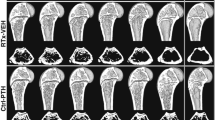

Our purpose was to characterize changes in bone remodeling associated with localized radiation that models therapeutic cancer treatment in ovary-intact (I) and ovariectomized (OVX) mice and to evaluate the influence of radiation on the pattern of bone mineral remodeling. Young adult, female BALB/c mice, I and OVX, were used (n = 71). All mice were intravenously injected with 15 μCi 45Ca. Thirty days post-45Ca administration, the hind limbs of 17 mice were exposed to a single dose of 16 Gy radiation (R). The time course of 45Ca excretion, serum CTx and osteocalcin markers, and cancellous bone volume fraction (BV/TV) and cortical thickness (Ct.Th) of the distal femur were assayed. Cellular activity and dynamic histomorphometry were performed. Irradiation resulted in rapid increases in fecal 45Ca excretion compared to control groups, indicating increased bone remodeling. CTx increased rapidly after irradiation, followed by an increase in osteocalcin concentration. BV/TV decreased in the I mice following irradiation. Ct.Th increased in the OVX groups following irradiation. I+R mice exhibited diminished osteoblast surface, osteoclast number, and mineral apposition. Our murine model showed the systemic effects (via 45Ca excretion) and local effects (via bone microarchitecture and surface activity) of clinically relevant, therapeutic radiation exposure. The I and OVX murine models have similar 45Ca excretion but different bone microarchitectural responses. The 45Ca assay effectively indicates the onset and rate of systemic bone mineral remodeling, providing real-time assessment of changes in bone histomorphometric parameters. Monitoring bone health via a bone mineral marker may help to identify the appropriate time for clinical intervention to preserve skeletal integrity.